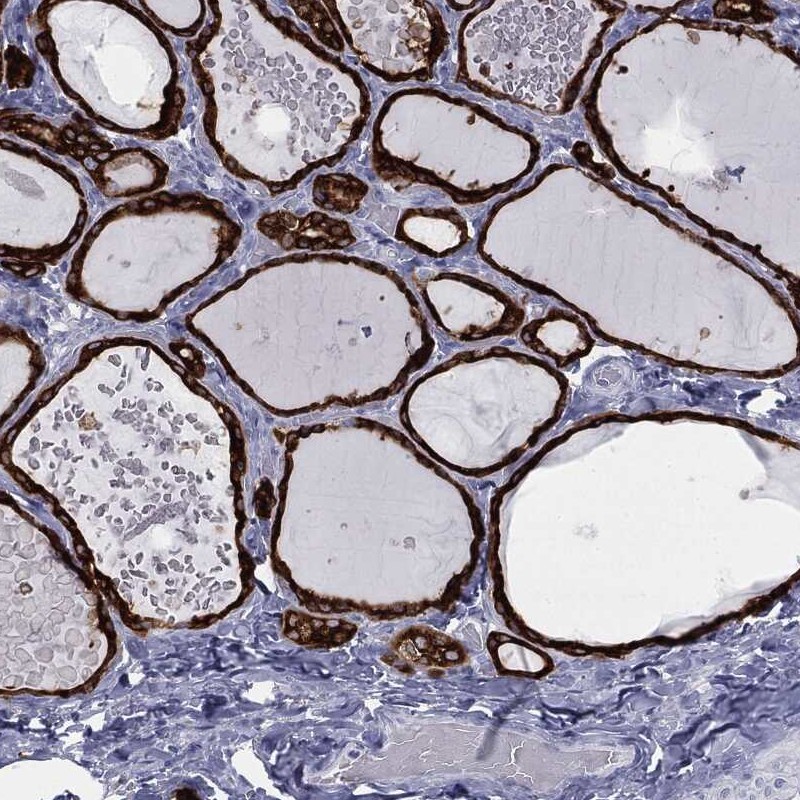

Immunohistochemical staining of human thyroid gland shows strong cytoplasmic positivity in glandular cells.